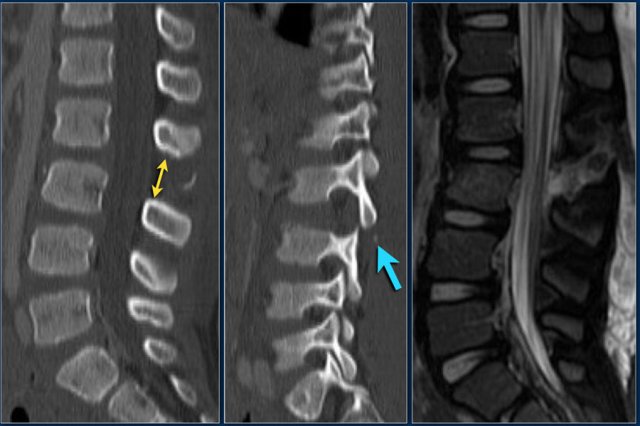

Case 5

Look at the images.

How would you describe the morphology and the PLC?

Then scroll to the next images.

The findings are:

1. Morphology: Burst - 2 points

There is retropulsion of a body fragment (black arrow)

2. PLC: widening of both facet joints (yellow arrow) and a fracture of spinous process (blue arrow) - 3 points

3. TLICS based on imaging: 5 points

Discussion: based on only these two images it is hard to say whether this is burst with PLC-injury or maybe distraction on the posterior side.

In either case the TLICS-score is high and this patient is a surgical candidate.